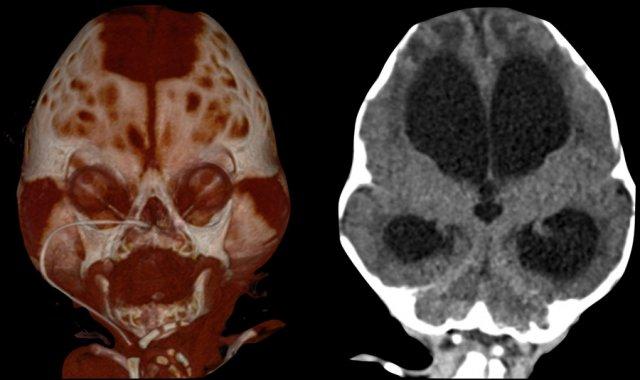

Biến chứng nội sọ

MRI đóng vai trò chủ đạo trong việc phát hiện các dị tật nội sọ kèm theo và các biến chứng từ dính khớp sọ đa đường khâu.

Hình ảnh

Tăng áp lực nội sọ.

TRÁI: Các vết ấn lõm trên phim X-quang sọ có độ nhạy thấp, đặc biệt ở trẻ nhỏ, nhưng khi xuất hiện, chúng rất gợi ý tình trạng tăng áp lực nội sọ.

PHẢI: Não úng thủy với dòng chảy tâm trương đảo ngược, biểu hiện của tăng áp lực nội sọ.

Các dấu hiệu có thể gợi ý tăng áp lực nội sọ được liệt kê trong bảng bên trái.

Mỗi dấu hiệu đơn lẻ không đặc hiệu, nhưng sự kết hợp của nhiều dấu hiệu cần làm tăng mức độ nghi ngờ.

Tăng áp lực nội sọ có thể dẫn đến hình thành các tuần hoàn bàng hệ tĩnh mạch, điều này có thể có ý nghĩa quan trọng trong lập kế hoạch phẫu thuật trước mổ.